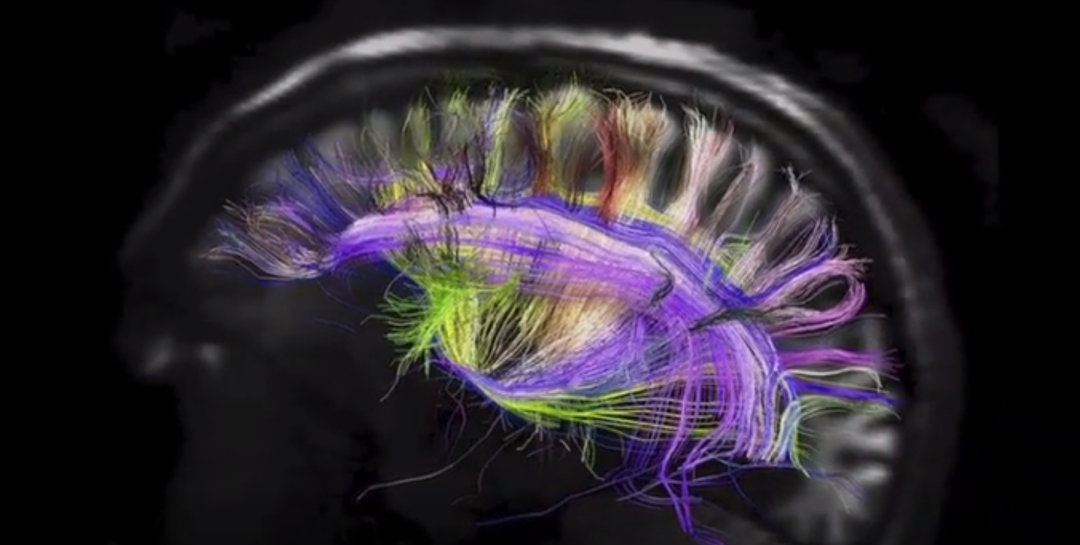

在过去的几年里,我们看到了一些显著的神经科学突破。在一项研究中,科学家们设法与瘫痪的病人进行交流,只要求他想象自己的想法,写下自己的想法。当他这样做时,大脑植入物记录了他运动皮层中的电信号,随后人工智能以94%的准确率解码了这些信号。在另一项研究中,科学家追踪了 "思想在大脑中的进展":参与者被要求思考一个特定单词的反义词,植入大脑皮层的电极显示了这个过程的每一步--刺激感知、单词选择和反应--是如何被 "传递 "到大脑的不同部分。在一项具有里程碑意义的研究中,科学家们声称终于找到了大脑中与“觉醒”和“意识”有关的三个特定区域,它们与意识的形成有关。

我最初是通过进化生物学家西蒙·康威·莫里斯(Simon Conway Morris)接触到这个观点的,他认为大脑不会“产生”意识,而是“遇到”意识,这种意识的“发现”是宇宙变得具有自我意识的一种方式(物理学家保罗·戴维斯(Paul Davies)提出了类似的观点,从无神论者的角度来看,哲学家托马斯·内格尔(Thomas Nagel)也提出了类似的观点)。神经学家保罗·努涅斯(Paul Nunez)和前欧洲核子研究中心(CERN)科学家贝尔纳多·卡斯特鲁普(Bernardo Kastrup)也初步提出了将大脑视为“天线”的想法。